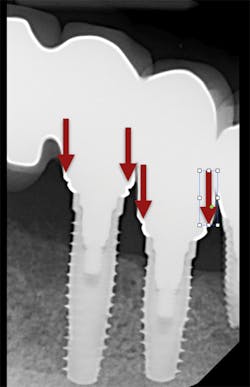

We all know that there are no shades of gray when it comes to the fit of implant-supported restorations—they either fit or they don’t. This makes the accuracy of our impressions especially important when we are fabricating implant-supported restorations. When implant-supported restorations do not fit, the results are increased chair time and appointments, reduced productivity, and increased frustration for both dentists and patients (figure 1).

1. Place your open-tray impression coping on the implant you are planning to impress. Confirm its complete seating with a radiograph (figure 4). There should not be a space at the junction of the implant and impression coping.